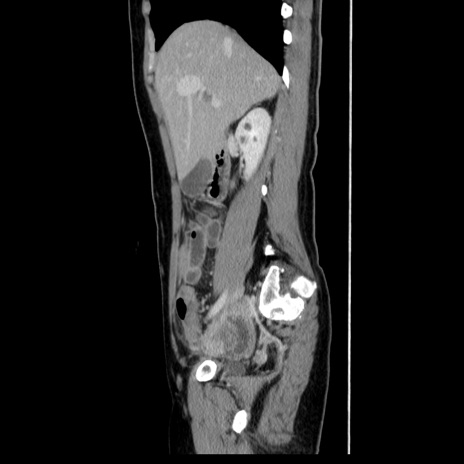

症例39(矢状断像)

【症例】40歳代女性

【主訴】上下腹部痛

【現病歴】2日目から下腹部痛あり。夜間は痛みで眠れなかった。昨日より上腹部痛と下痢が出現。臥位で痛みは軽快したため、休んでいた。本日になって臥位でも立位でも痛みが強くなってきたため救急要請。

【既往歴】子宮内膜症

【身体所見】部:平坦・軟、左上下腹部に圧痛あり、反跳痛あり。

【データ】WBC 21800、CRP 26.78

CT

MRI(4日後)